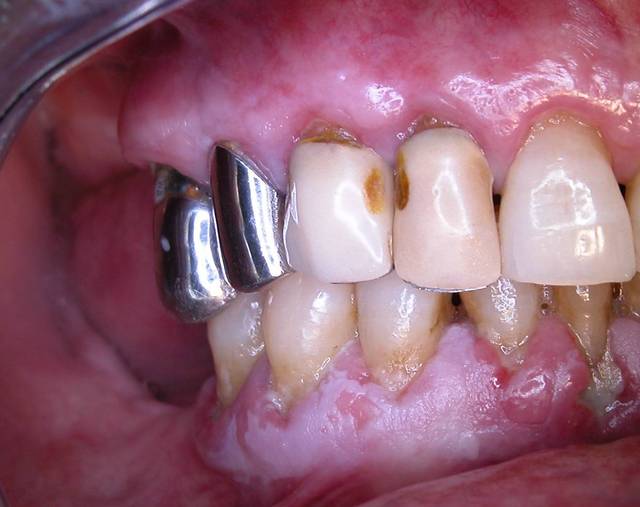

je vois une patiente en consultation, aujourd'hui. Elle se plaint de problèmes de gencives qui saignent... Quand vous verrez les photos vous comprendrez pourquoi.

Le problème, n'est pas la parodontite, mais des lésions blanches, situées surtout à la mandibule. La patiente ne fume pas et ces lésions ne partent pas au grattage.

Alors lichen plan ou kératose?

c'est adhérent mais cela un toucher granité.

lichen plan presque sur ......

il me semble que le pemphigus et l'erythème polymorphe sont des maladies bulleuses avec des signes généraux souvent associés et des lésions des joues et des lèvres à un stade développé .......pour cette patiente dont les lésions sont évoluées tout semble localisé sur la gencive .......pour avoir vu beaucoup de lichen plan j'ai tendance à penser à cela avec une leucoplasie associée par endroit

Tout dépend de l'HDM (histoire de la maladie) pour l'extension, sinon effectivement le diagnostic macroscopique est complexe, mais oon retrouve un aspect placardant en mosaïque, je serai curieux d'avoir le résultat de la biopsie, je m'avoue un peu sec devant la photo, et incertain

D'après un confrère spécialisé en pathologie buccale, c'est donc un lichen. Merci les gars.